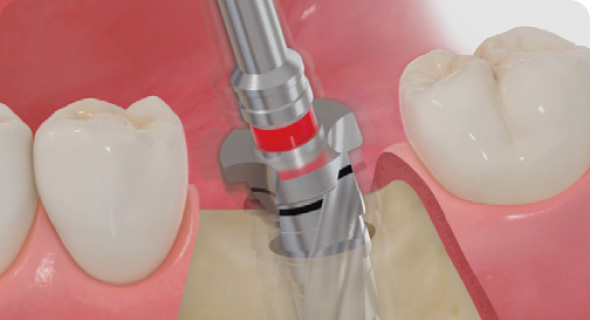

STEP 03

네비게이션 수술

- 원가이드 구강 장착

- 정확하고 안전한 수술